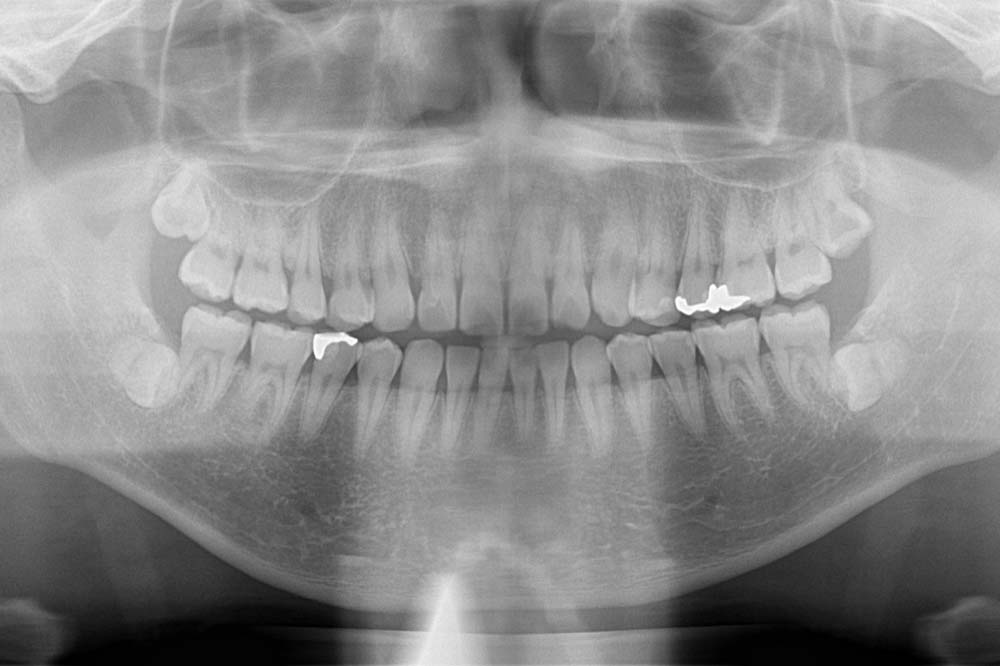

ここで一番注意したいのは『下の歯で横に向いている親知らず』です。

このタイプの親知らずは、手前の歯との隙間に汚れが溜まりやすい状態です。

その結果、手前の歯を虫歯にしてしまうケースが非常に多いです。

さらに、この状態での虫歯は発生位置が通常と異なります。

最初から非常に深い位置での虫歯になってしまい、気づいた時には処置不能といったことも起こり得ます。

そのため、症状が無くても抜歯をおすすめする場合があります。